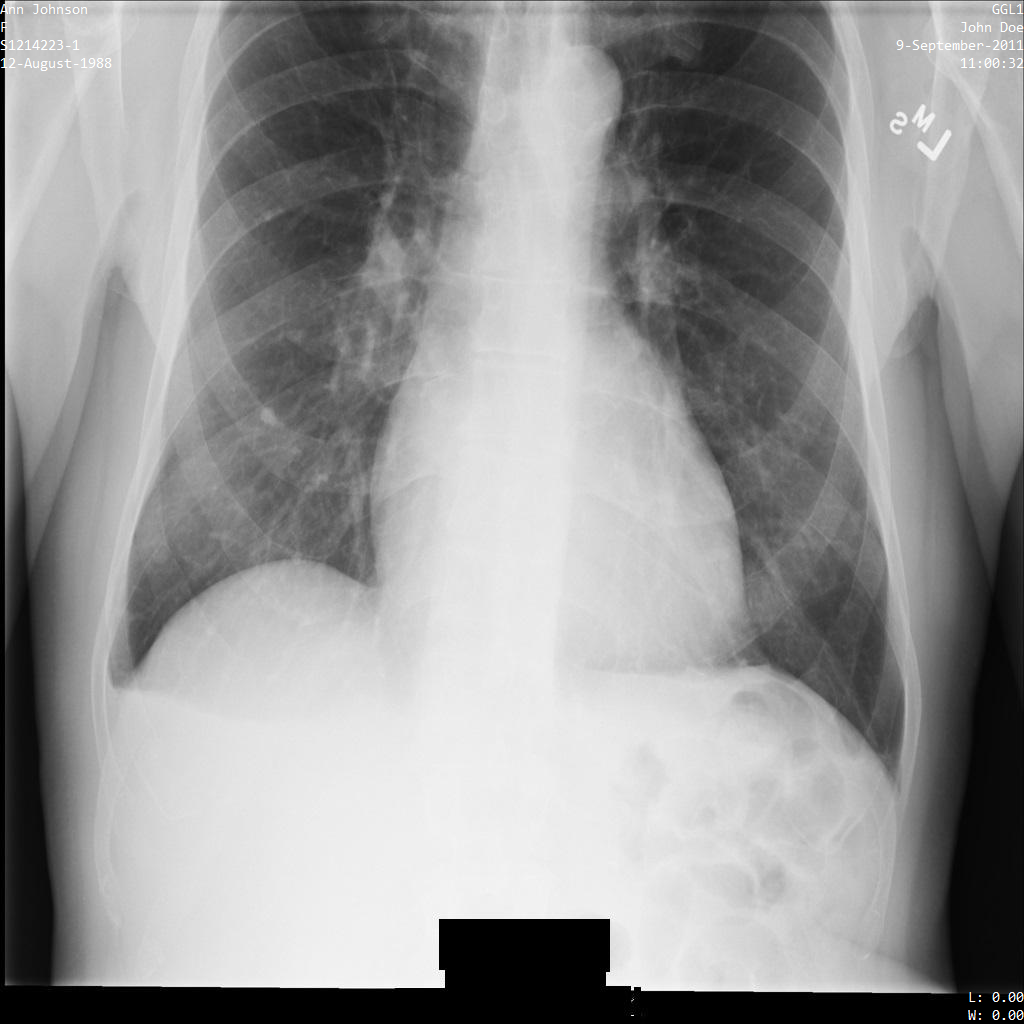

Setiap bagian berikut memberikan contoh cara melakukan de-identifikasi data DICOM menggunakan berbagai metode. Output gambar yang tidak diidentifikasi disediakan dengan setiap sampel. Setiap sampel menggunakan gambar asli berikut sebagai input:

Anda dapat membandingkan gambar output dari setiap operasi penghapusan identitas dengan gambar asli ini untuk melihat efek operasi.

Setelah mengirimkan gambar ke Cloud Healthcare API, gambar akan muncul seperti berikut. Meskipun metadata yang ditampilkan di sudut atas gambar telah disamarkan, informasi kesehatan terlindungi (PHI) yang tercetak di bagian bawah gambar tetap ada. Untuk juga menghapus teks sisipan, lihat Menyamarkan teks sisipan dari gambar.

REST